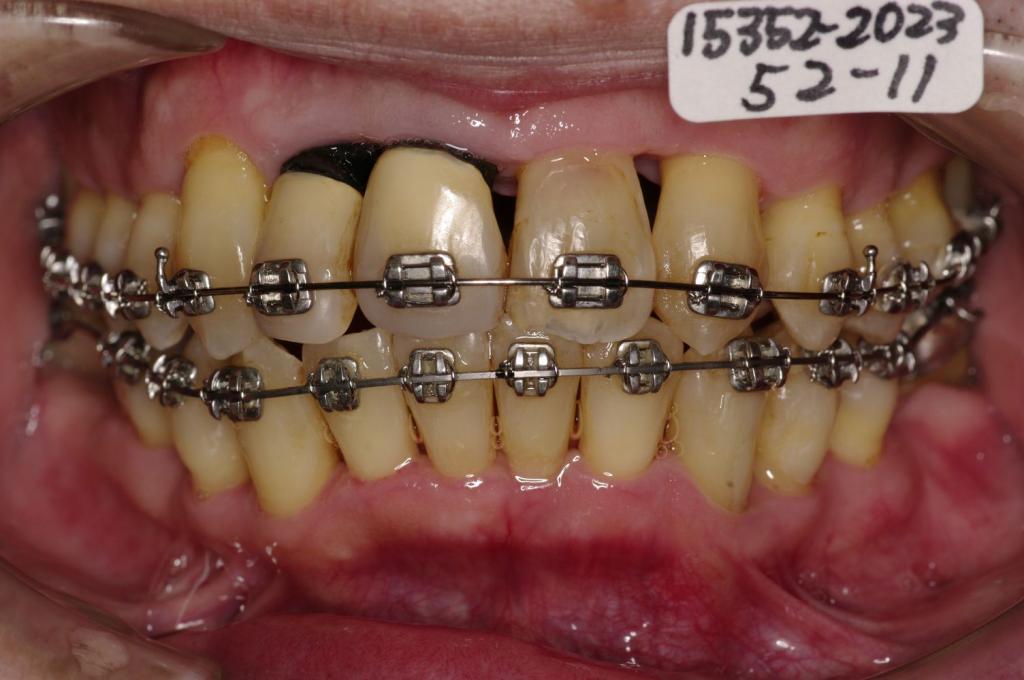

- 歯周病を伴った矯正治療

- 歯磨きがし難い